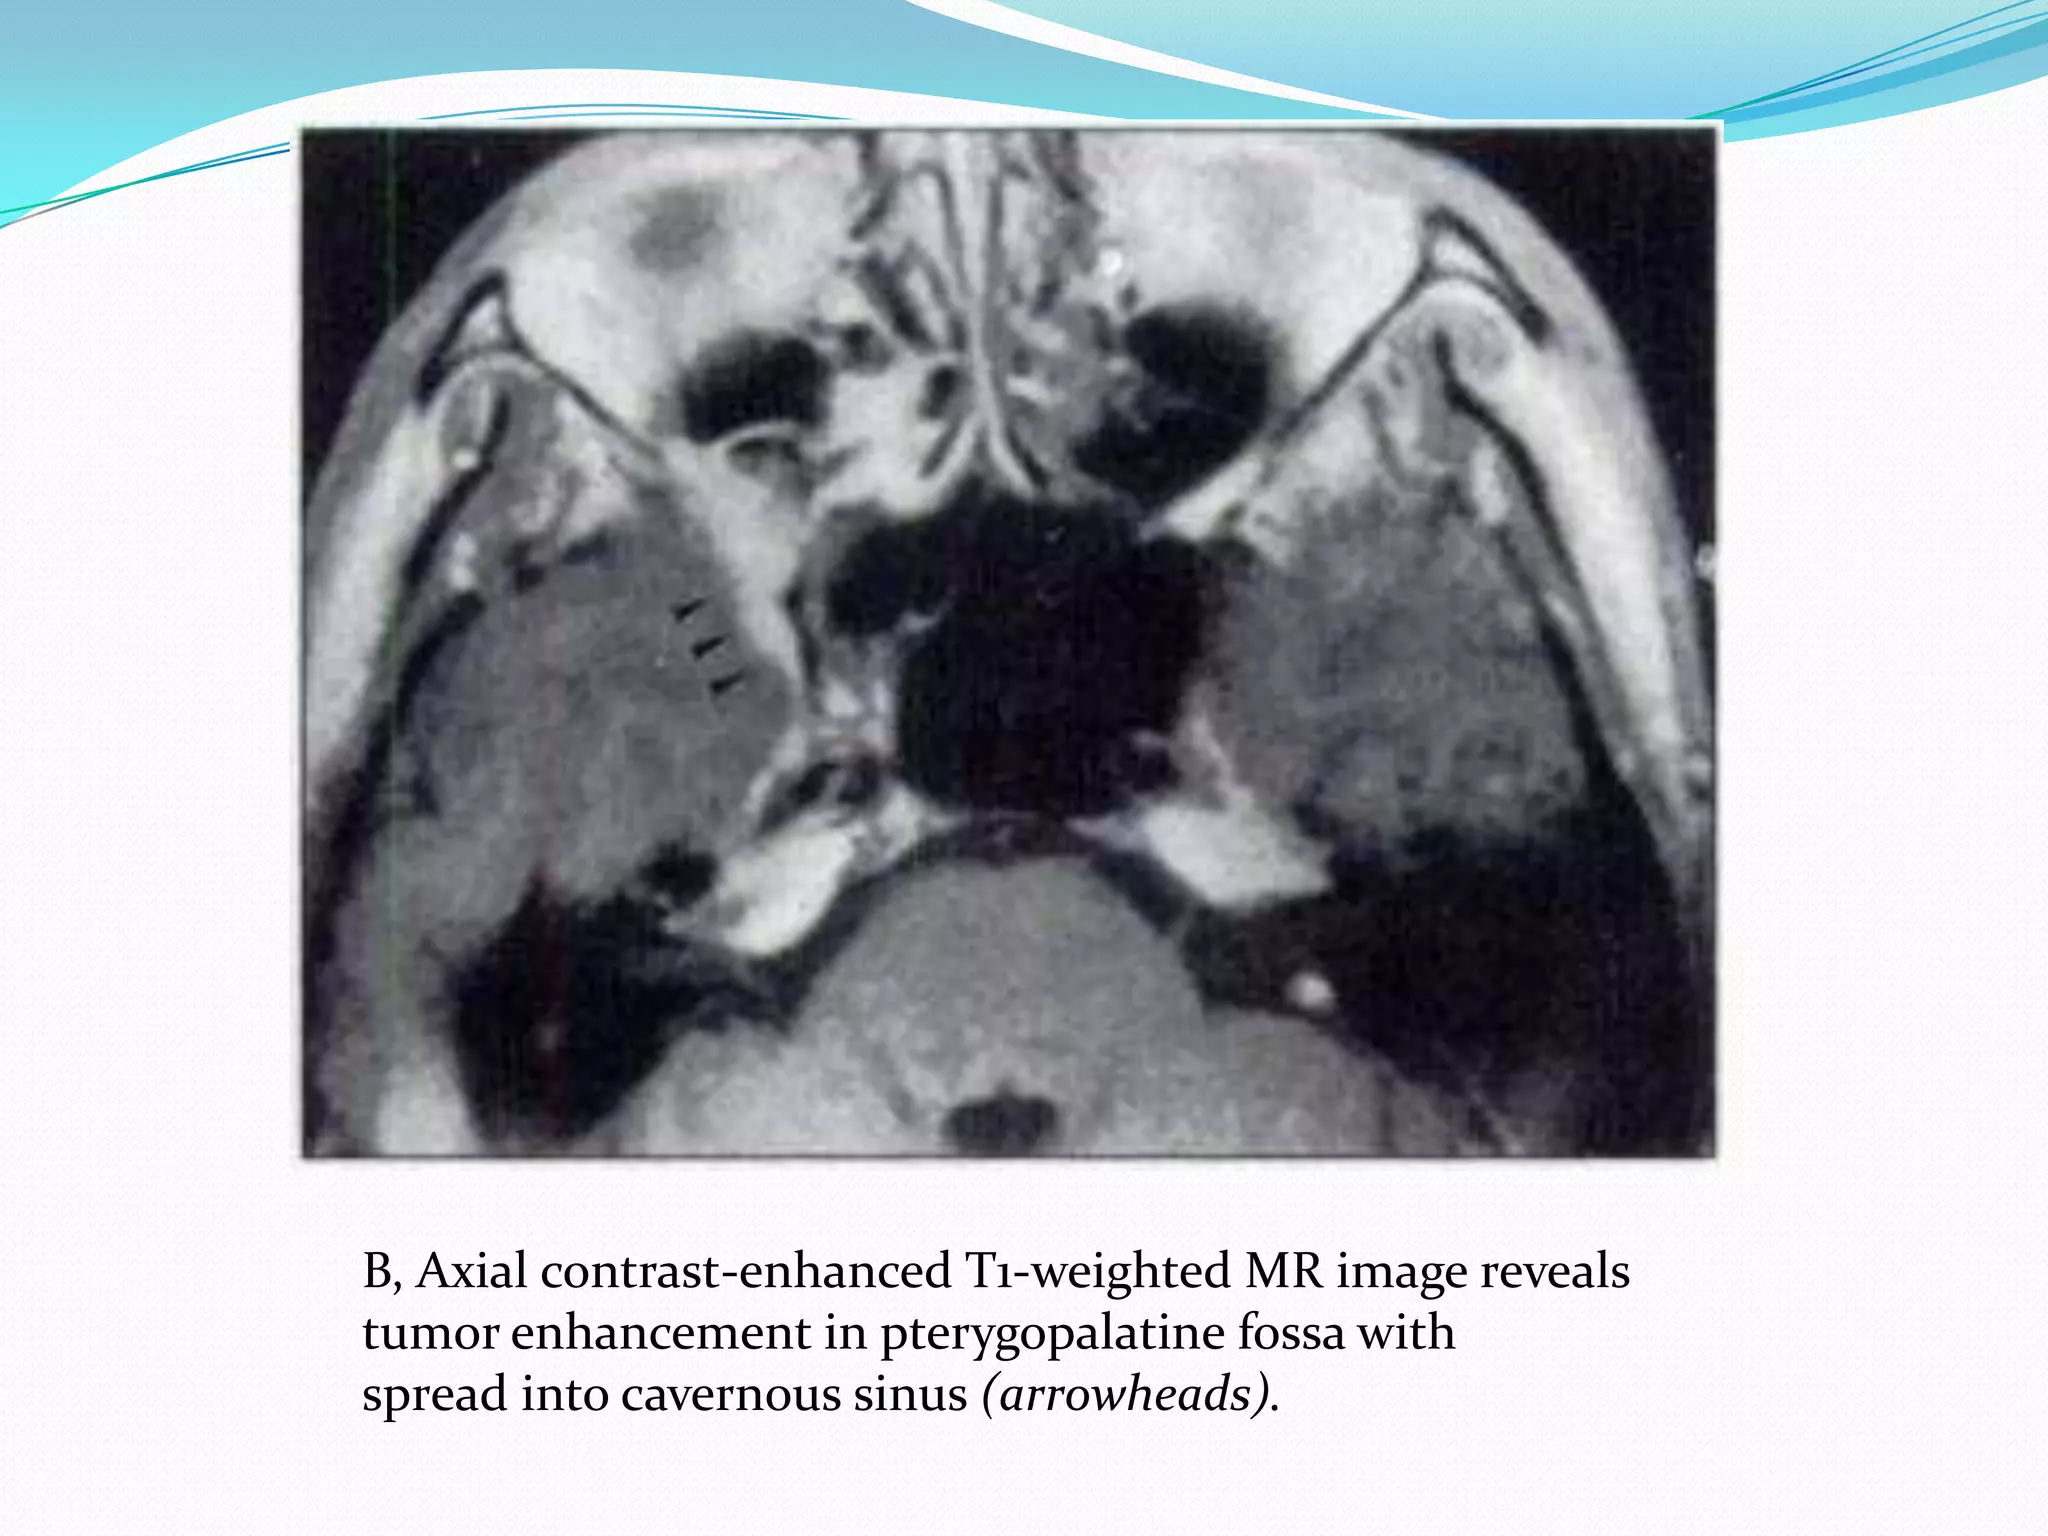

B, Axial contrast-enhanced T1-weighted MR image reveals

tumor enhancement in pterygopalatine fossa with

spread into cavernous sinus (arrowheads).